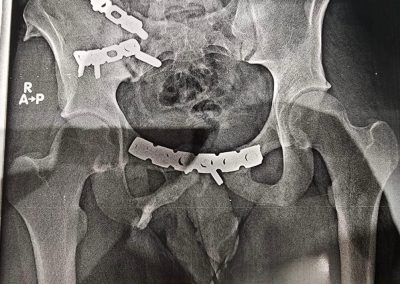

ياسين محمد أمين العمر:١٧ عامًا اصيب بكسر غير ثابت متفتت بالحوض يناير ٢٠٢٣